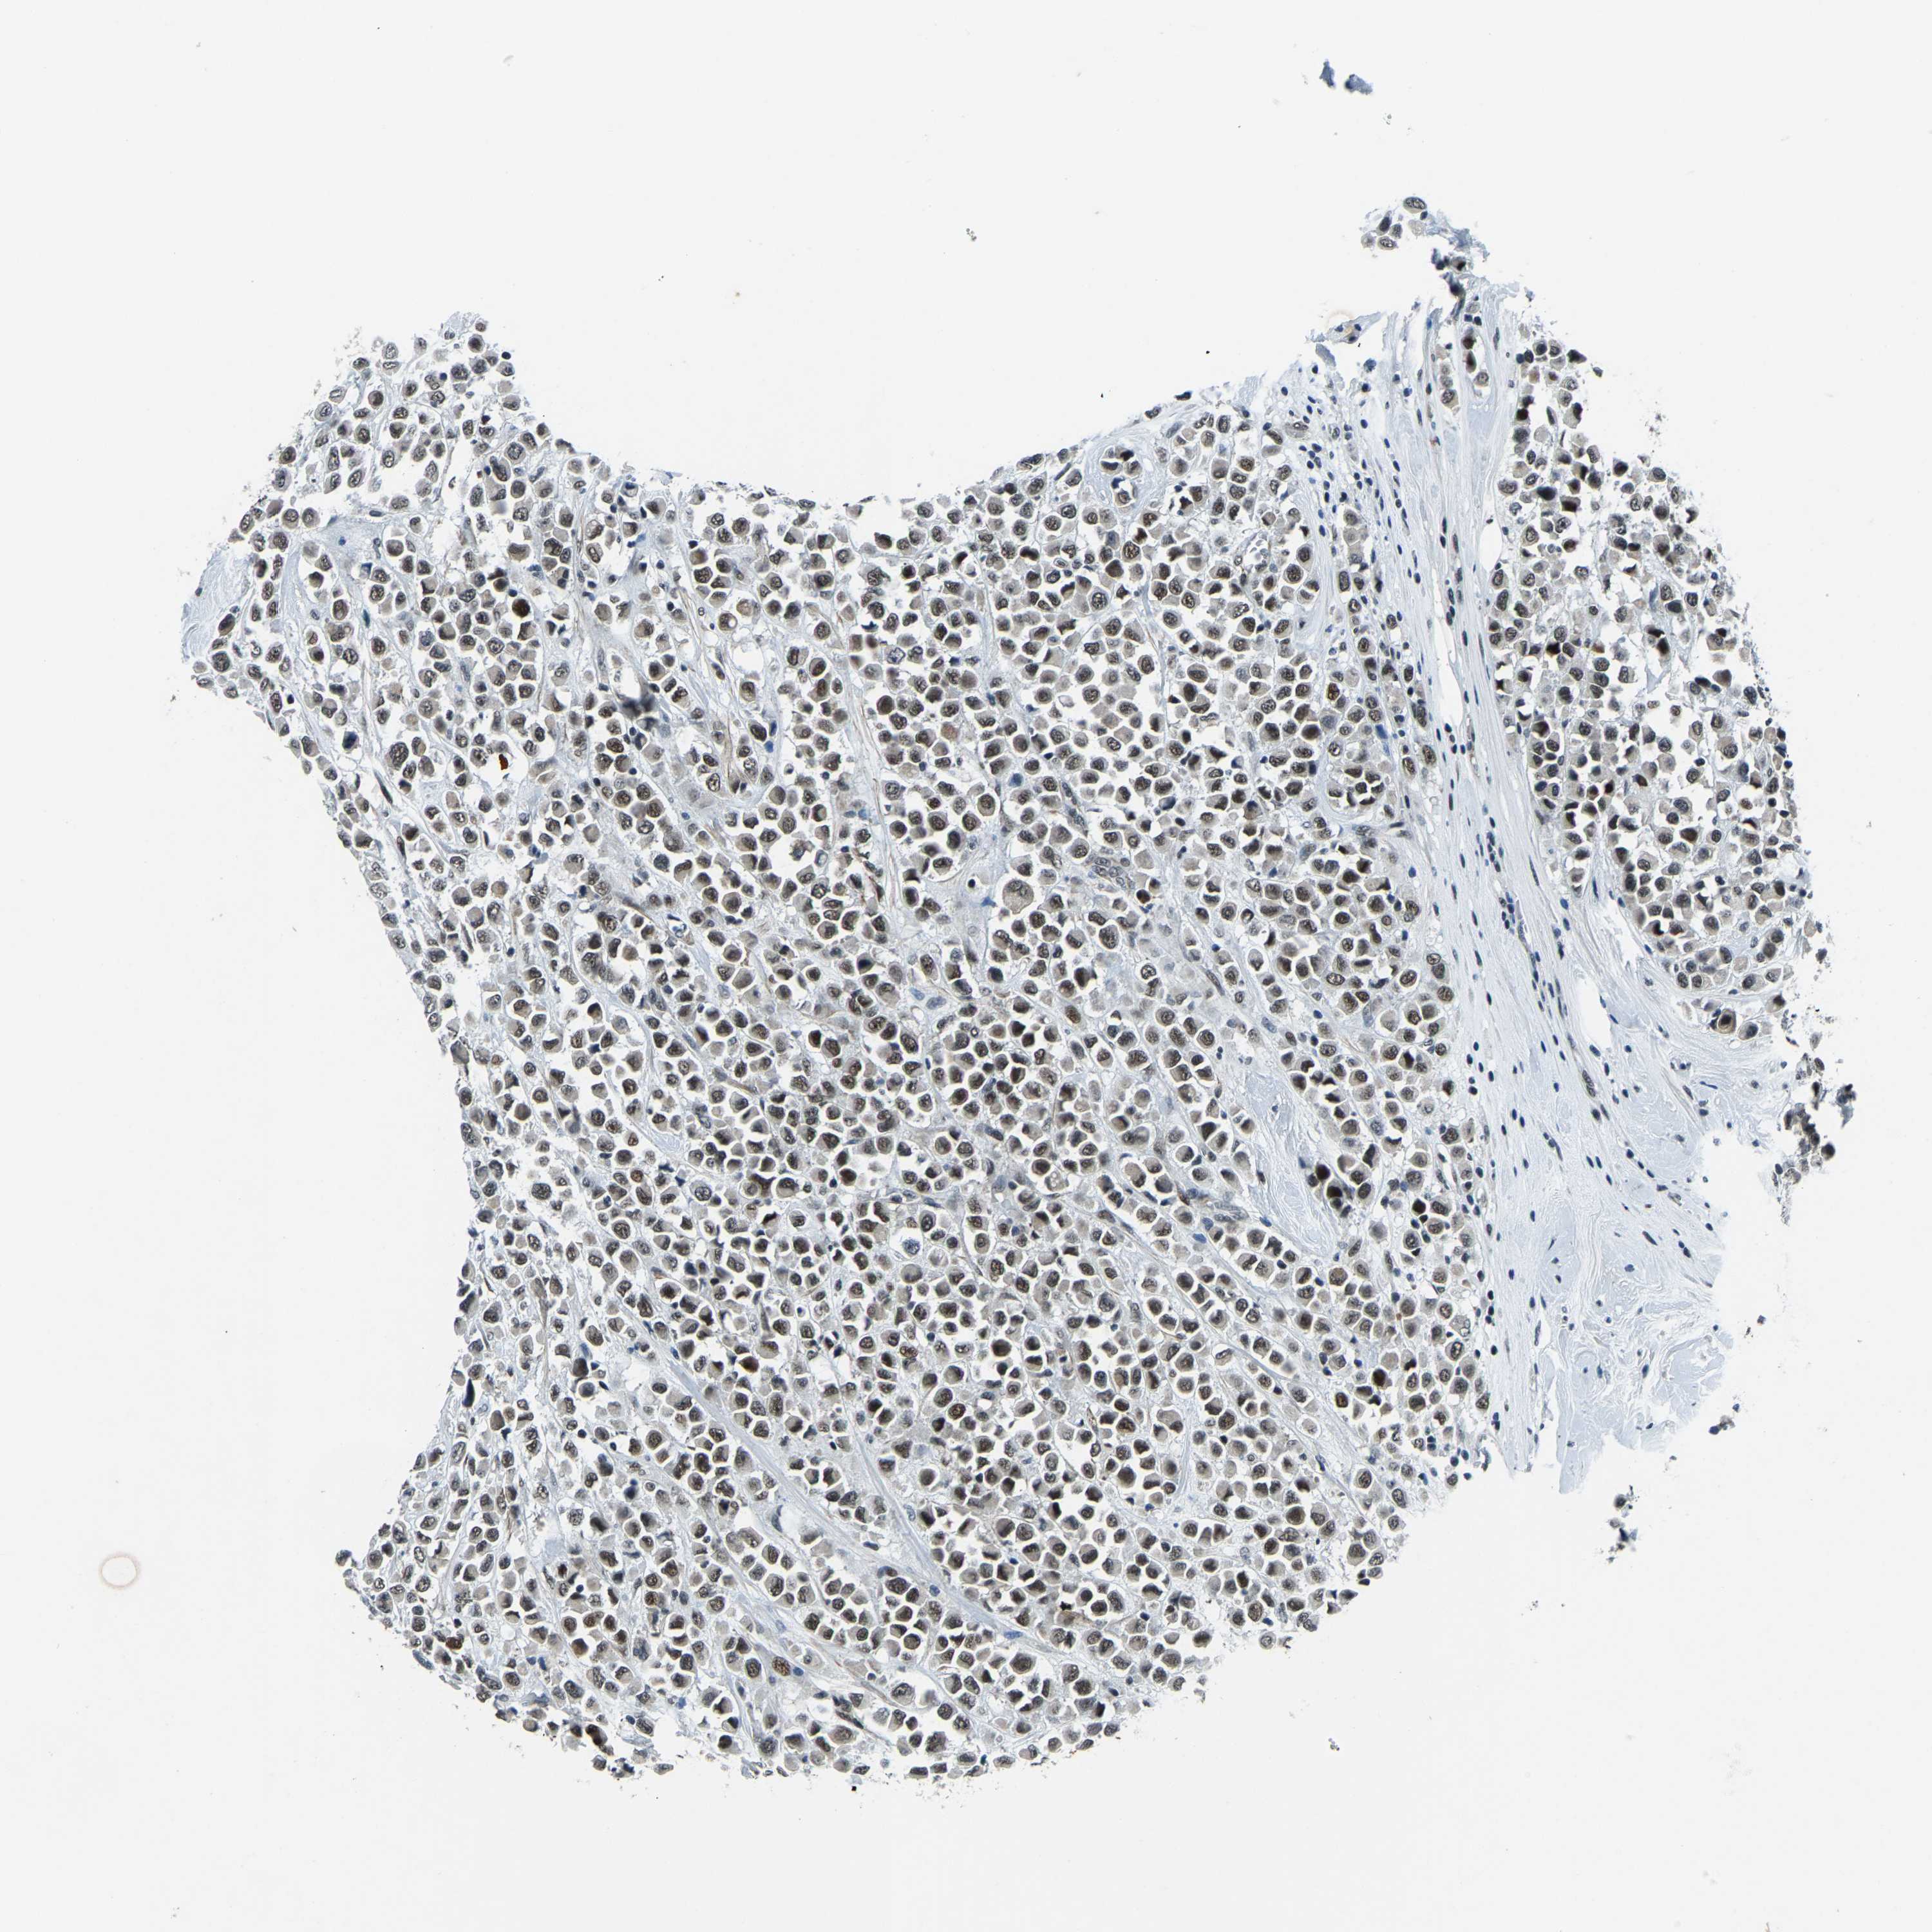

CANCER BREAST CANCER Show tissue menu

BRCA TCGA BRCA VALIDATION PROTEIN EXPRESSION